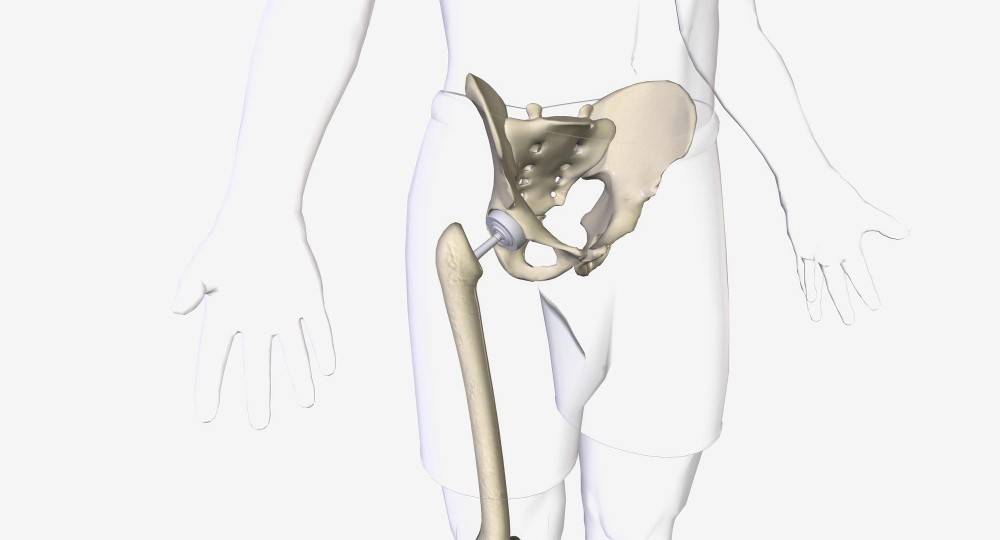

What is pelviacetabular surgery? It involves repairing the pelvic and hip bones that may have been injured due to accidents or falls. The pelvis supports your organs and helps in movement, and this surgery is key to restoring its function. It’s significant because it addresses severe fractures that can affect daily living.

The surgeon uses specific methods to access the injured area. The choice depends on fracture type and the patient’s condition. Techniques might include open surgery or minimally invasive methods.

- Open Surgery: This involves a larger incision for direct access to the bones. It’s often used for severe injuries.

- Minimally Invasive Surgery: This uses smaller cuts and special equipment. Although suitable for certain fractures, it reduces recovery time and risks.

Each technique has its benefits. Open surgeries offer a clear view, aiding complex repairs, while minimally invasive ones shorten hospital stays and speed recovery.